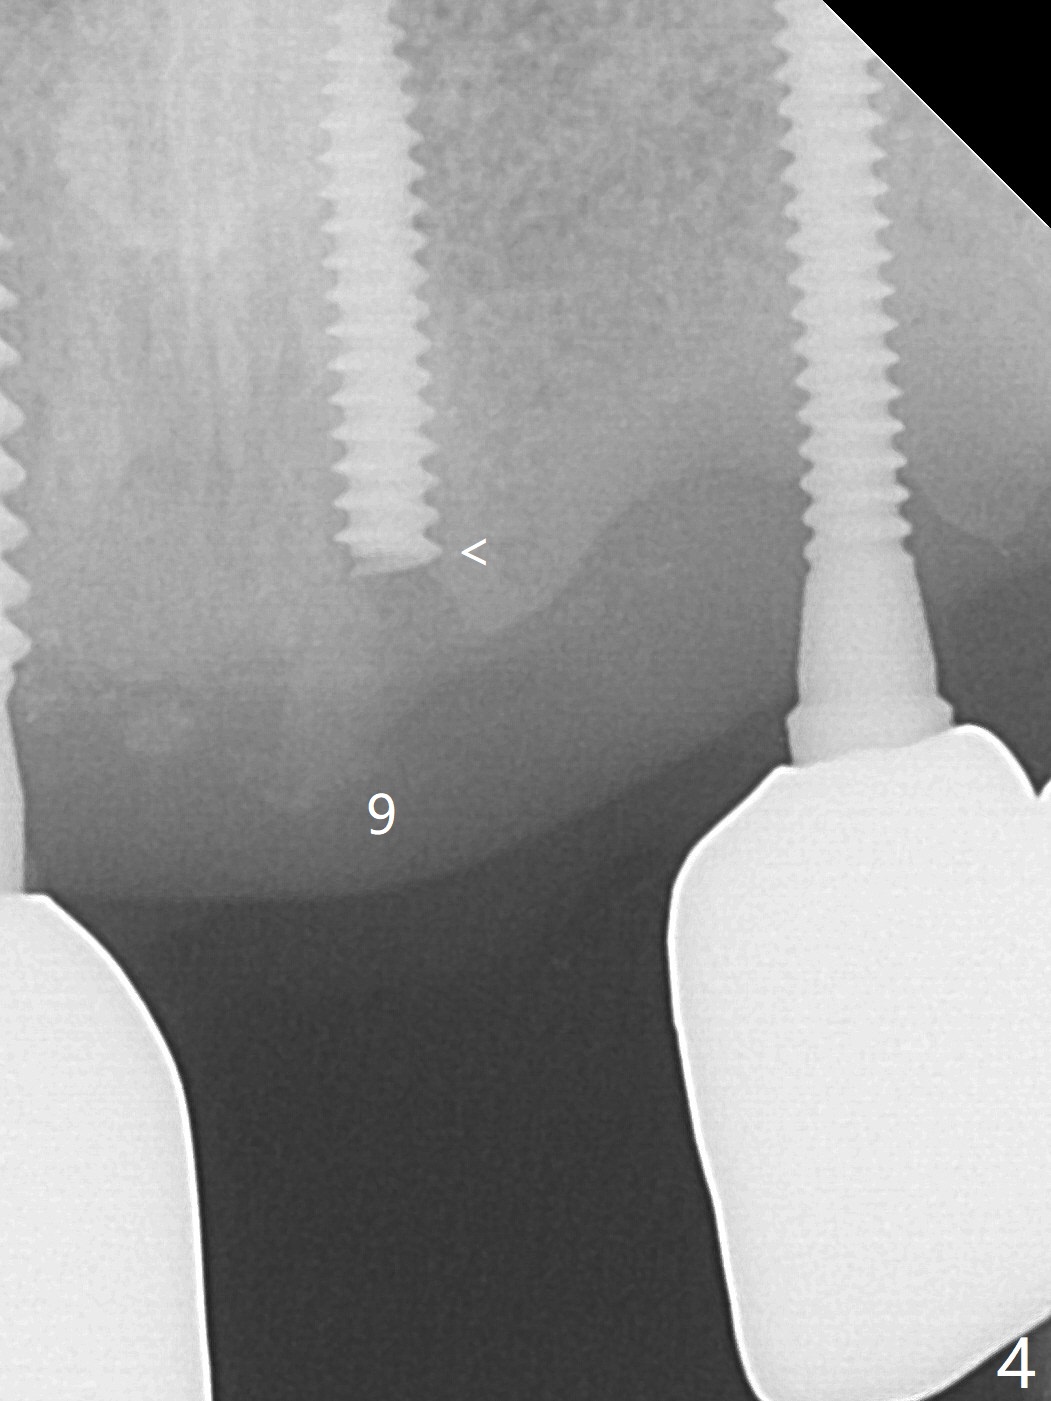

The implant access at #9 closes 1 week post implant fracture (Fig.1,4). There is mild gingival erythema at #10 (Fig.2,3 ^). There is bone around the fractured implant, which is palatally placed (Fig.5). The 2 mm implant is removed using 2/3 mm trephine bur. In spite of moving the osteotomy buccally, a 4.5x4 mm, 15 degree A-type angled abutment is installed for an immediate provisional following placement of a 3.5x10 mm implant (Fig.7, 25 Ncm). Sticky bone is placed (Fig.7 *) palatal to the implants at #9 and 10 (with thread exposure, Fig.6). While the majority of periodontal dressing remains in place (Fig.9,10), the suture in the exposed area appears to hold the papilla in place (Fig.8 <). Herpetic infection develops in the palate (Fig.9). Two months later, the gingiva at #10 is healthy; it appears that the implant threads are covered by bone graft. The immediate provisional (fabricated before suture) keeps the gingiva in an ideal position for impression of final restoration. It appears that the access hole is in a right area for screw retained restoration. The gingival cuff is healthy immediate pre-cementation, 4 months postop (Fig.12,13). The lab does not make access hole for the final crown (Fig.14). The implant remains subcrestal 4 months postop (Fig.15). Since the shade of the crown is off, the abutment remains un-torqued and the crown is cemented with temp bond. The implant threads at #10 seem to be covered by bone graft 4 months postop (Fig.16).